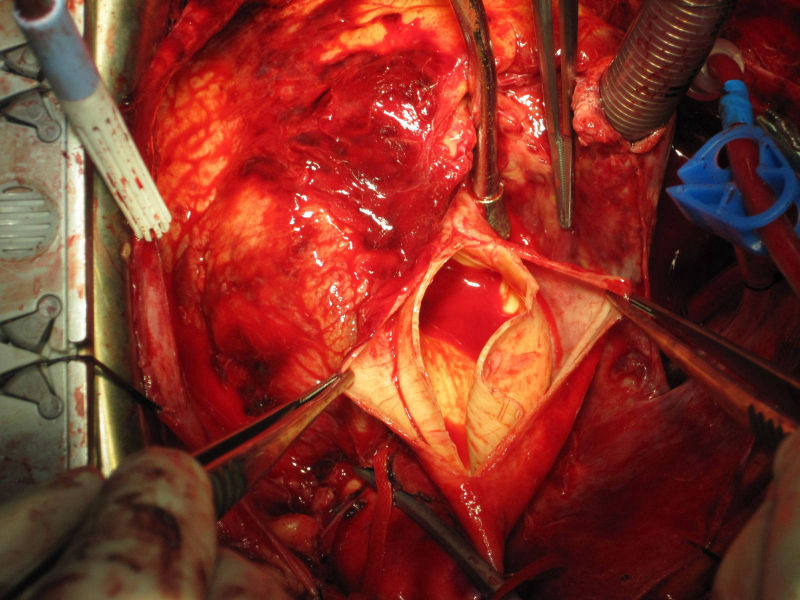

Mitral Valve Repair

Wherever possible, repair of the mitral valve is performed. This is superior to replacement since it retains the native valve. We have excellent long term results (over 20 years) with no significant leak.